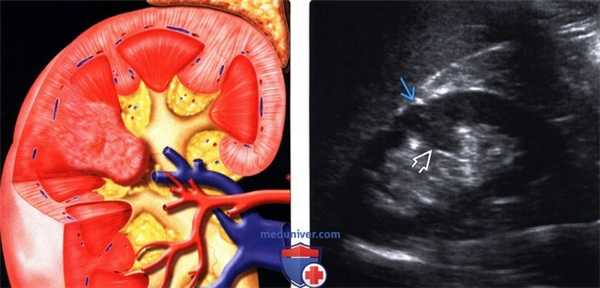

(Левый) На рисунке показана бертиниева колонна, которая является не истинным новообразованием, а разрастанием коркового вещества почки между пирамидами.

(Правый) На продольном ультразвуковом срезе правой почки визуализируется гипертрофированная колонна Бертена, вдающаяся в клетчатку почечной пазухи в среднем отделе почки. Обратите внимание на ее изоэхогенность корковому веществу и гладкие наружные контуры.